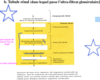

ils filtrent continuellement le sang et plus particulièrement le plasma (150 à 180 L/jour) et n’excrètent qu’environ 1% de ce volume (1,5 à 1,8 L/jour) sous forme d’urine

Quel est le role des reins?

rôle important dans la régulation du volume et de la composition chimique du sang (équilibre hydroélectrolytique, pH)

Qu’est ce qui est excrété et réabsorbé par les reins?

- excrétion dans l’urine des déchets métaboliques, toxines, substances chimiques, etc.

- mais réabsorption de substances indispensables à l’équilibre du milieu intérieur (régulation de l’homéostasie)